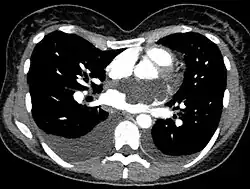

Myxom des Herzens

Lokalisation

Der Tumor kann in allen vier Herzhöhlen vorkommen, findet sich aber zu 85 % im linken Vorhof.[4]

Makroskopisch handelt es sich um eine kugelförmige polypöse oder zottige Geschwulst mit weicher gallertartiger Konsistenz. Obwohl der Tumor histologisch mit einem Thrombus in Organisation verwechselt werden kann, leitet er sich pathogenetisch von einer echten Neoplasie undifferenzierter endokardialer Mesenchymzellen ab. Die Tumoren werden im Durchschnitt 5–6 cm groß und haften dem Endokard in der Regel gestielt an (selten breitbasig).